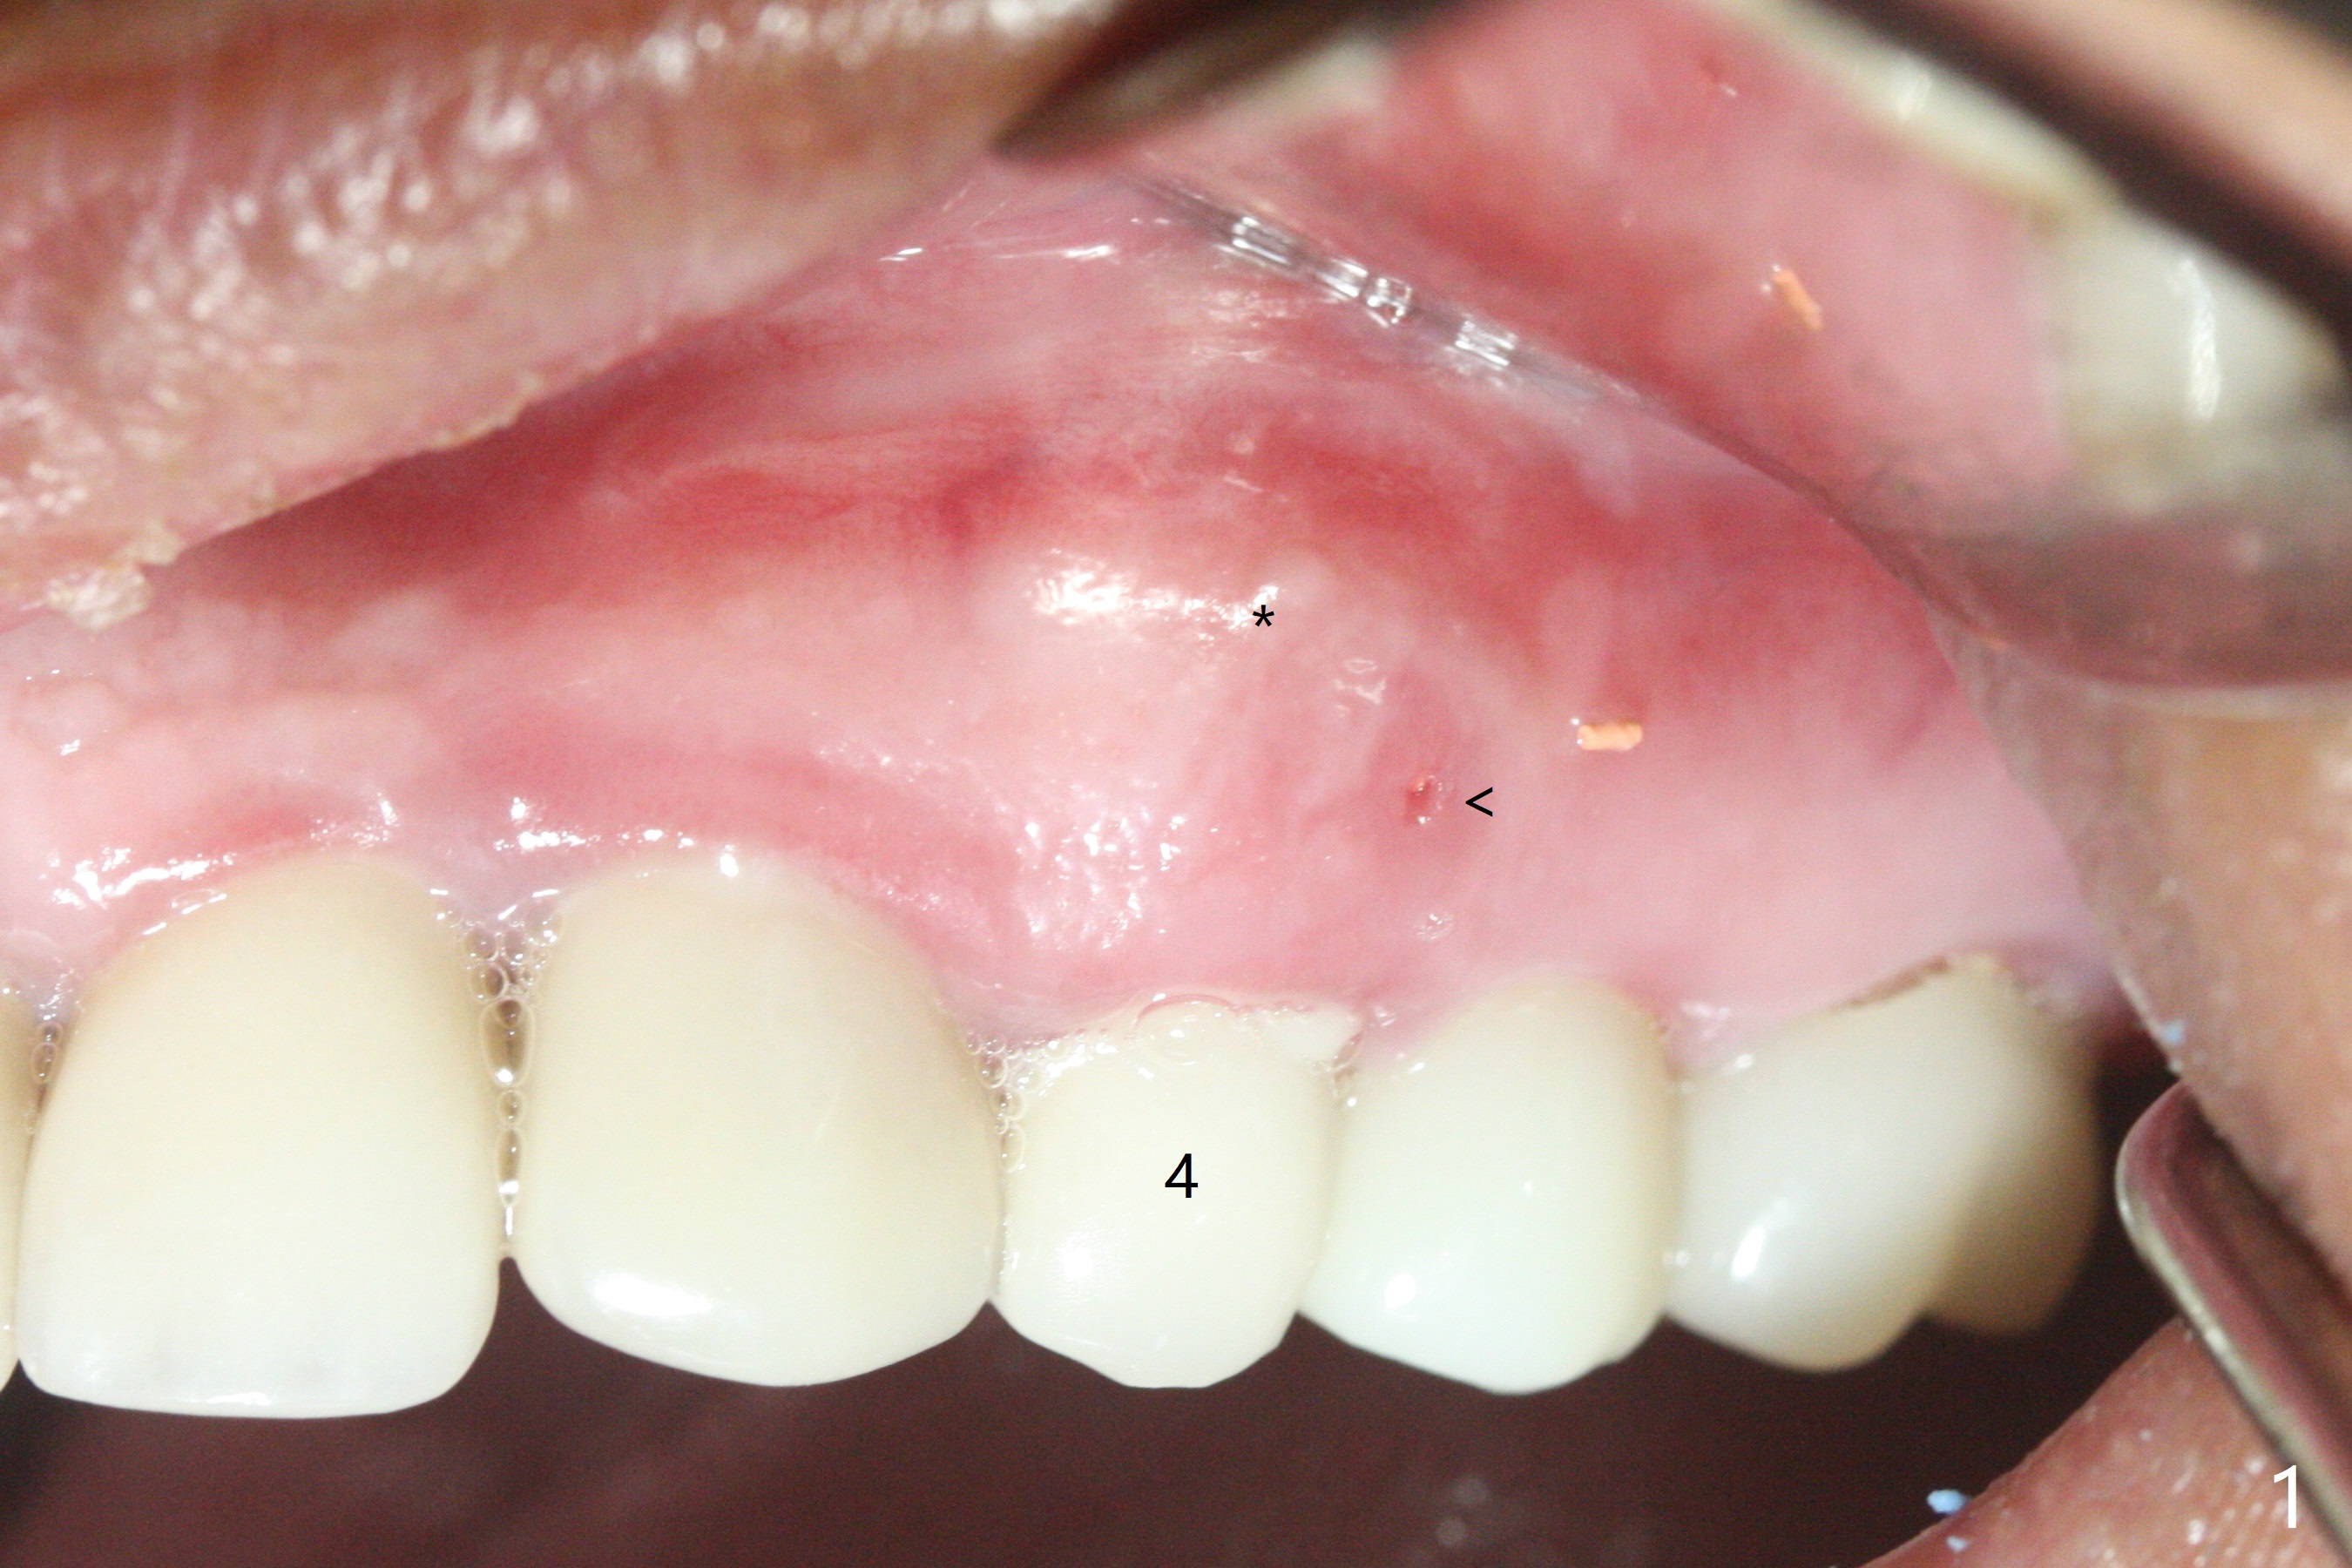

52岁女左上4颊侧牙龈显著肿胀(图一:*(颊侧骨板缺失))伴有瘘道(<),拔除前,在3植牙牙冠切缘舌侧形成开口(图二:*,准备纠正基台不全就位(<);4初步钻洞不正。改变钻头方向后(图三),完成植体放置(图四),并且安置修复基台(4.5x4(2))。磨去3牙冠近中面(图六:*),牙冠和基台反时针旋转(图六:弯箭头),基台完全就位(图四:箭头),调𬌗后,制作4临时牙冠(图六),放置后者前,覆盖半张PRF膜(促进下面粘性骨粉愈合)。图五,六颊侧隆起是因为下面放置许多粘性骨粉。图七是术前CT3D图像(冠状切面),显示颊侧(B),腭侧(P)牙根。拔牙后显示中隔(图八:S),植体植入腭侧窝(图九:绿色),四面骨质包绕,包括中隔;为了修复颊侧骨板,首先放置半张PRF膜(红色)紧贴颊侧骨板腭侧/牙龈,防止骨粉从瘘道流失,然后放置粘性骨粉(图十:粉红色)。术后2.5月3颊侧牙龈仍然红肿(图十一,十二:*),可能与基台袖太短有关(2毫米,图二至四),所以更换袖3毫米的基台(图十三)。术后四个月(牙冠粘固)3颊侧牙龈炎症明显减退(资料没有显示)。术后2.5月4颊侧骨板没有塌陷(图十二,与术后即刻对比(图六))。3基台放置太颊侧,所以在牙冠腭侧制作小的开口(图十四:>),让多余粘固剂流出。取模前3螺丝就拧紧(35Ncm),而4由于有大的开口,粘固后才拧紧(30Ncm)。两个邻牙其中一个可以取出,容易去除另外一个牙冠残余粘固剂。